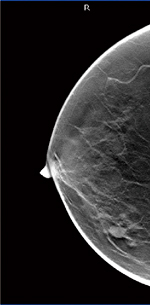

右CC画像 |

右トモシンセシス画像 |